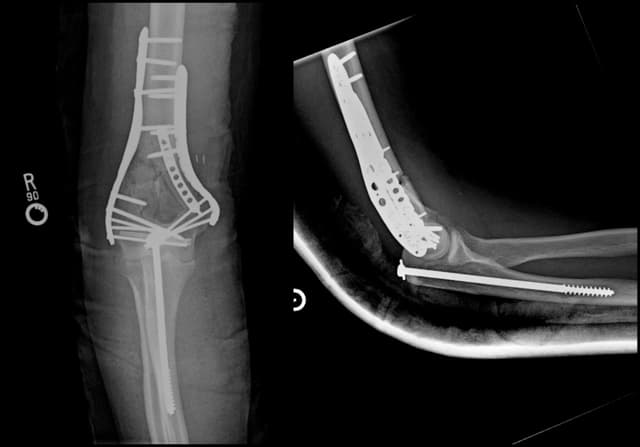

Intra-articular Distal Humerus ORIF

Post-op